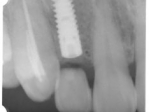

埋入直後のレントゲン。上部に見えるのは抜いた歯を利用して両どなりの歯に接着して一時的に使えるようにした。